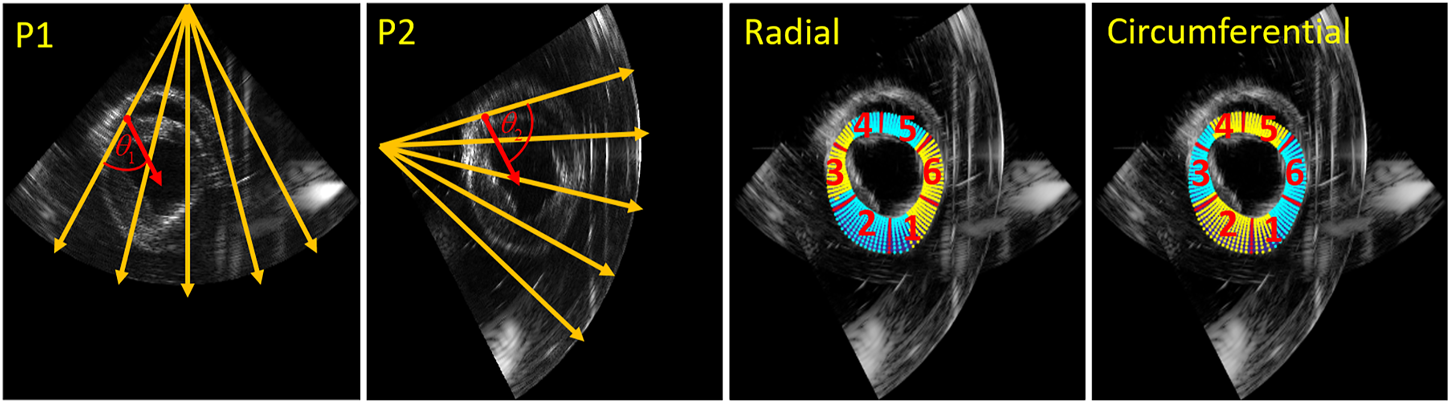

Strain Fusion

The second method to improve strain estimation is to fuse the strain instead of compounding the displacements, so-called strain fusion (SF). Derived radial and circumferential strain of the two probes for all relative angle datasets were fused based on automatically generated strain fusion masks. In the first step, for each point in the segmentation mesh (11 by 90 samples in total), the angle between strain and US beam direction was calculated for both probes. Next, all the calculated angles in the mesh of the two probes were compared, where the smaller angles were selected to create the masks for strain fusion. Finally, as Figure 5 shows, the masks for radial and circumferential strain fusion were created, where cyan shows strain selected from probe 1 (P1) and yellow indicates strain chosen from probe 2 (P2). Furthermore, the mesh was segmented into six regions for regional strain analysis [42].

FIGURE 5

Strain fusion: an example on how to select the optimal radial strain from the two probes for in this case a relative angle of 75° (left two images). The orange arrows indicate the US beam directions, the red arrows indicate the radial strain direction of the red point for the two probes respectively. and are the angles between US beam and the radial strain direction of the red point respectively. Masks for radial and circumferential strain fusion (right two images), where cyan means strain selected from P1 and yellow indicates strain chosen from P2. Red numbers show the segmented myocardial regions (11 by 90 samples) for regional strain analysis.